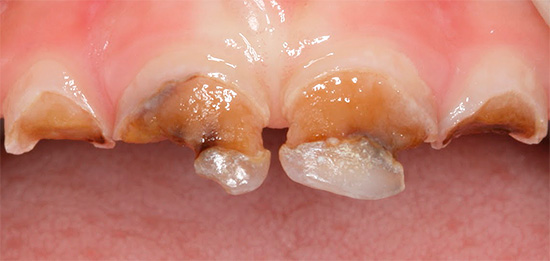

Un aspetto tipico dei denti con carie cronica è mostrato nella foto qui sotto:

Non ci sono lesioni estese dei denti e in alcuni punti le aree scure sono di dimensioni molto ridotte e spesso non attirano l'attenzione del paziente. Di solito il dolore è assente.

La carie cronica può essere osservata anche nei denti primari. Questa è una delle malattie più comuni nei bambini, poiché può essere difficile per i genitori tenere traccia delle condizioni dei loro denti in tenera età. A volte il dentista deve affrontare i problemi del decorso acuto della carie, quando in pochi mesi la carie del bambino nella fase spot si trasforma in profonde violazioni del tessuto dentale. In questo caso, è necessario interrompere immediatamente il suo sviluppo conducendo un trattamento complesso di tutti i fuochi.

Vi sono prove che la carie cronica nei bambini può essere determinata già su denti permanenti eruttati. Il principio del suo sviluppo è lo stesso del morso di latte.